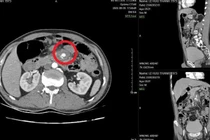

Tăm tre đâm vào mạch máu tạo giả phình mạch nguy cơ vỡ mạch đe dọa tính mạng Sức khoẻ 360 23/10/2025 19:22 Nguy hiểm hơn khi đầu tăm tiếp tục đâm vào một trong những mạch máu lớn nhất trong ổ bụng có thể gây vỡ mạch, chảy máu ồ ạt trong ổ bụng, đe dọa tính mạng.